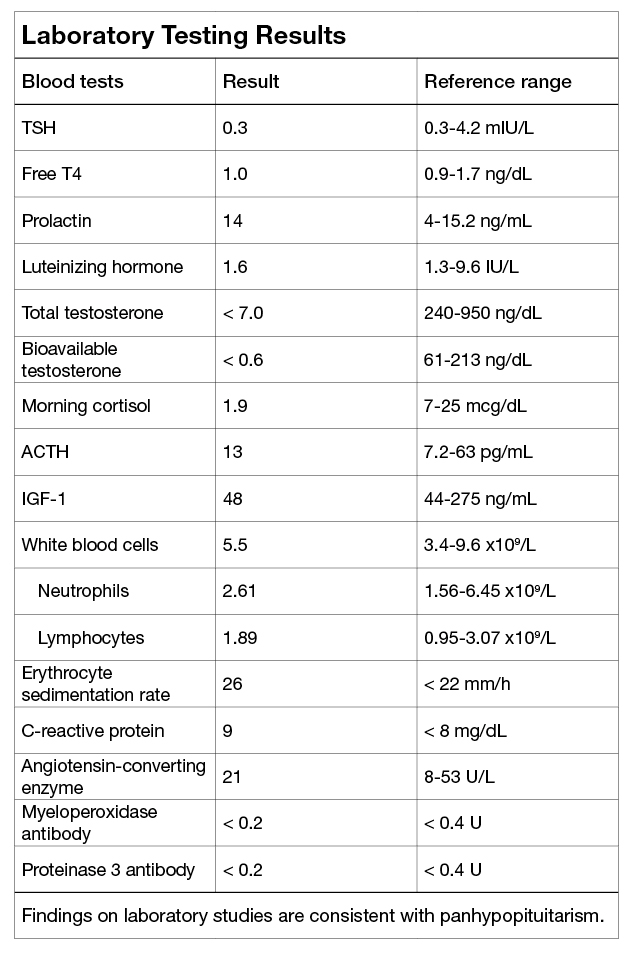

Laboratory testing results

Laboratory testing results

Findings on laboratory studies are consistent with panhypopituitarism.

Findings on laboratory studies were consistent with panhypopituitarism.